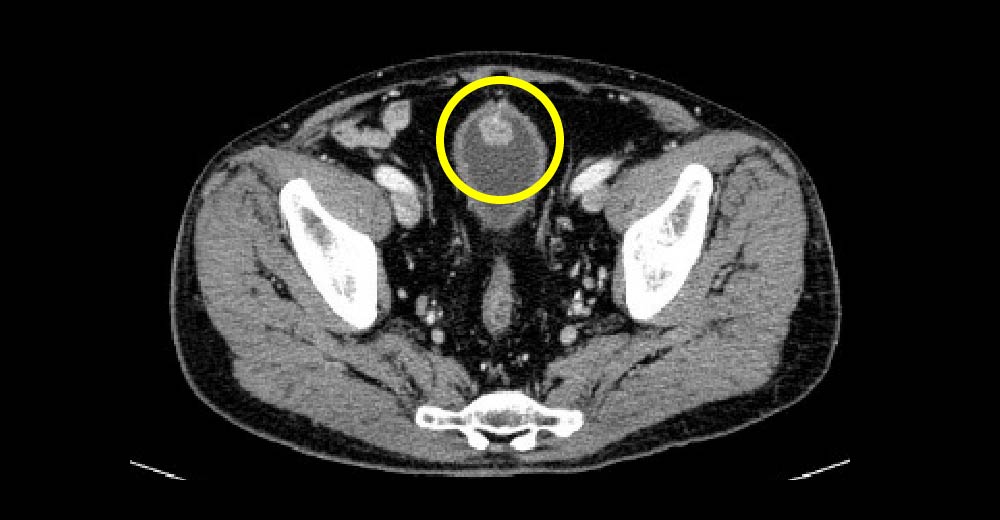

腎細胞がん症例です。

エコーで、内部不均一な腫瘤が確認されます。

腎細胞がん 腎細胞がん

造影CTにおいて、不整な造影効果を伴う腫瘤が確認されます